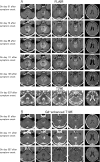

Up to one-third of lymphoma cases involve the nervous system. Miller-Fisher syndrome (MFS) associated with lymphoma is extremely rare. We herein report a case of primary central nervous system lymphoma initially mimicking MFS in a 70-year-old man who presented with subacute unsteady gait and diplopia. A neurological examination revealed unilateral ophthalmoplegia, ataxia, and areflexia. The patient tested positive for anti-GQ1b antibodies, so MFS was initially suspected. However, the progression extended over one month. Subsequently, disturbance of consciousness was observed. Cranial magnetic resonance imaging revealed lesions in the periventricular fourth ventricle, and a brain biopsy indicated diffuse large B-cell lymphoma.